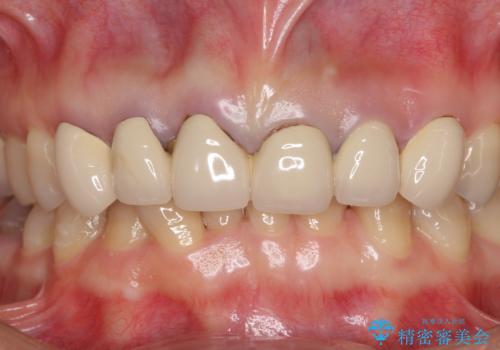

下の前歯がほとんど隠れてしまうほどの深い咬み合わせで、咬合力も強いため、治療期間中は仮歯が外れやすく、ご迷惑をおかけしました。

セラミッククラウン装着後は、とても自然な口元に仕上がりました。